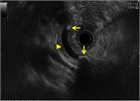

1. 膵管内の結石(膵石)を認めた場合と、膵全体に分布する複数かつびまん性の石灰化を認めた場合は慢性膵炎と診断できる(推奨度1)

1. 加齢現象に伴い膵石が観察される場合がある。

1. 石灰化を伴った膵腫瘍がまれに存在する。